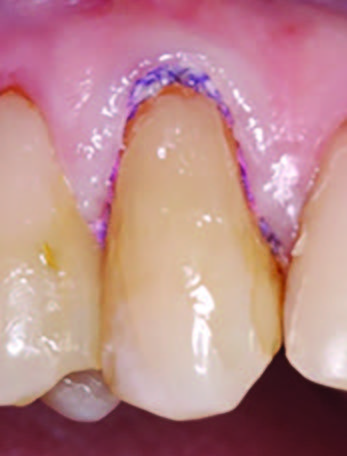

Figure 1.

Initial presentation of tooth #6 showing the Class V lesion with dislodged previous restoration and exposed dentin.